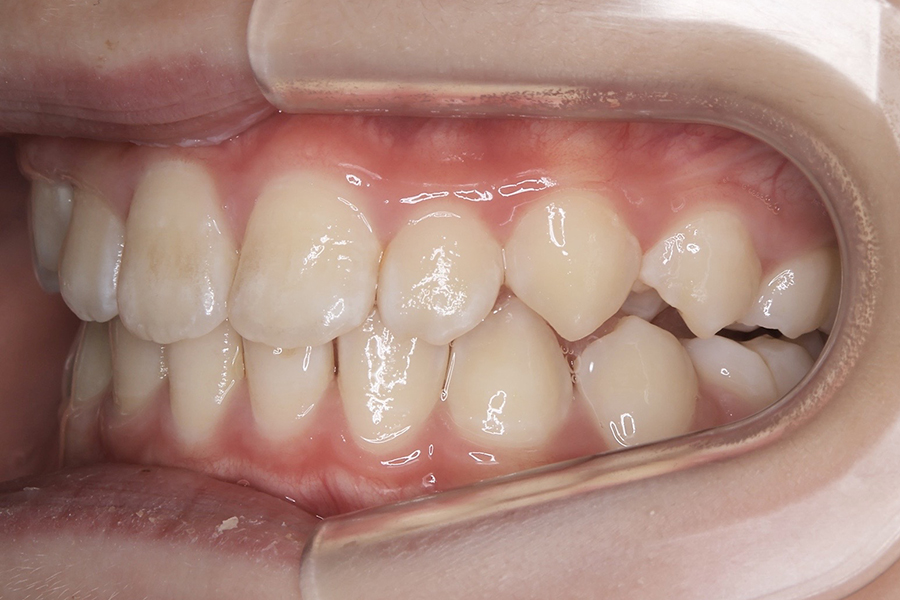

FDT症例② S.Hくん(10)

治療前

相談内容 |

うつ伏せ寝、口呼吸が気になる 歯並びの悪さ |

カウンセリング・診断結果 |

口呼吸、低位舌、上下顎劣成 |

行った治療内容 |

FDT(筋機能矯正治療/マイオブレース治療) |

治癒期間 |

2024.8.31〜 |

費用 |

385,000円(税込) |

治療リスクについて |

・お子様・保護者の協力が必要。 |

担当者からのコメント |

頑張り屋さんで真面目なHくん。正面から見ると一見綺麗ですが、横から見た時の前歯の出っ張りや永久歯の生えるスペースがないためFDTを始めました。 |